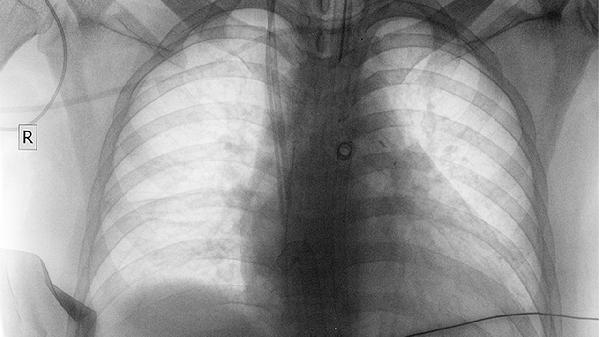

2、诊断背痛是否为肺癌引起,需结合影像学检查如胸部CT、MRI或PET-CT,以及肿瘤标志物检测。若怀疑骨转移,可进行骨扫描或骨活检。早期发现有助于提高治疗效果。